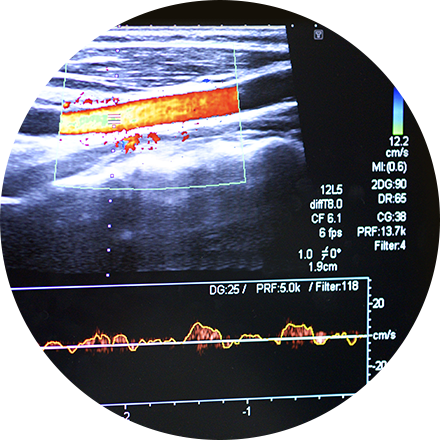

• Doppler ultrasound (to visualize blood flow through a blood vessel).